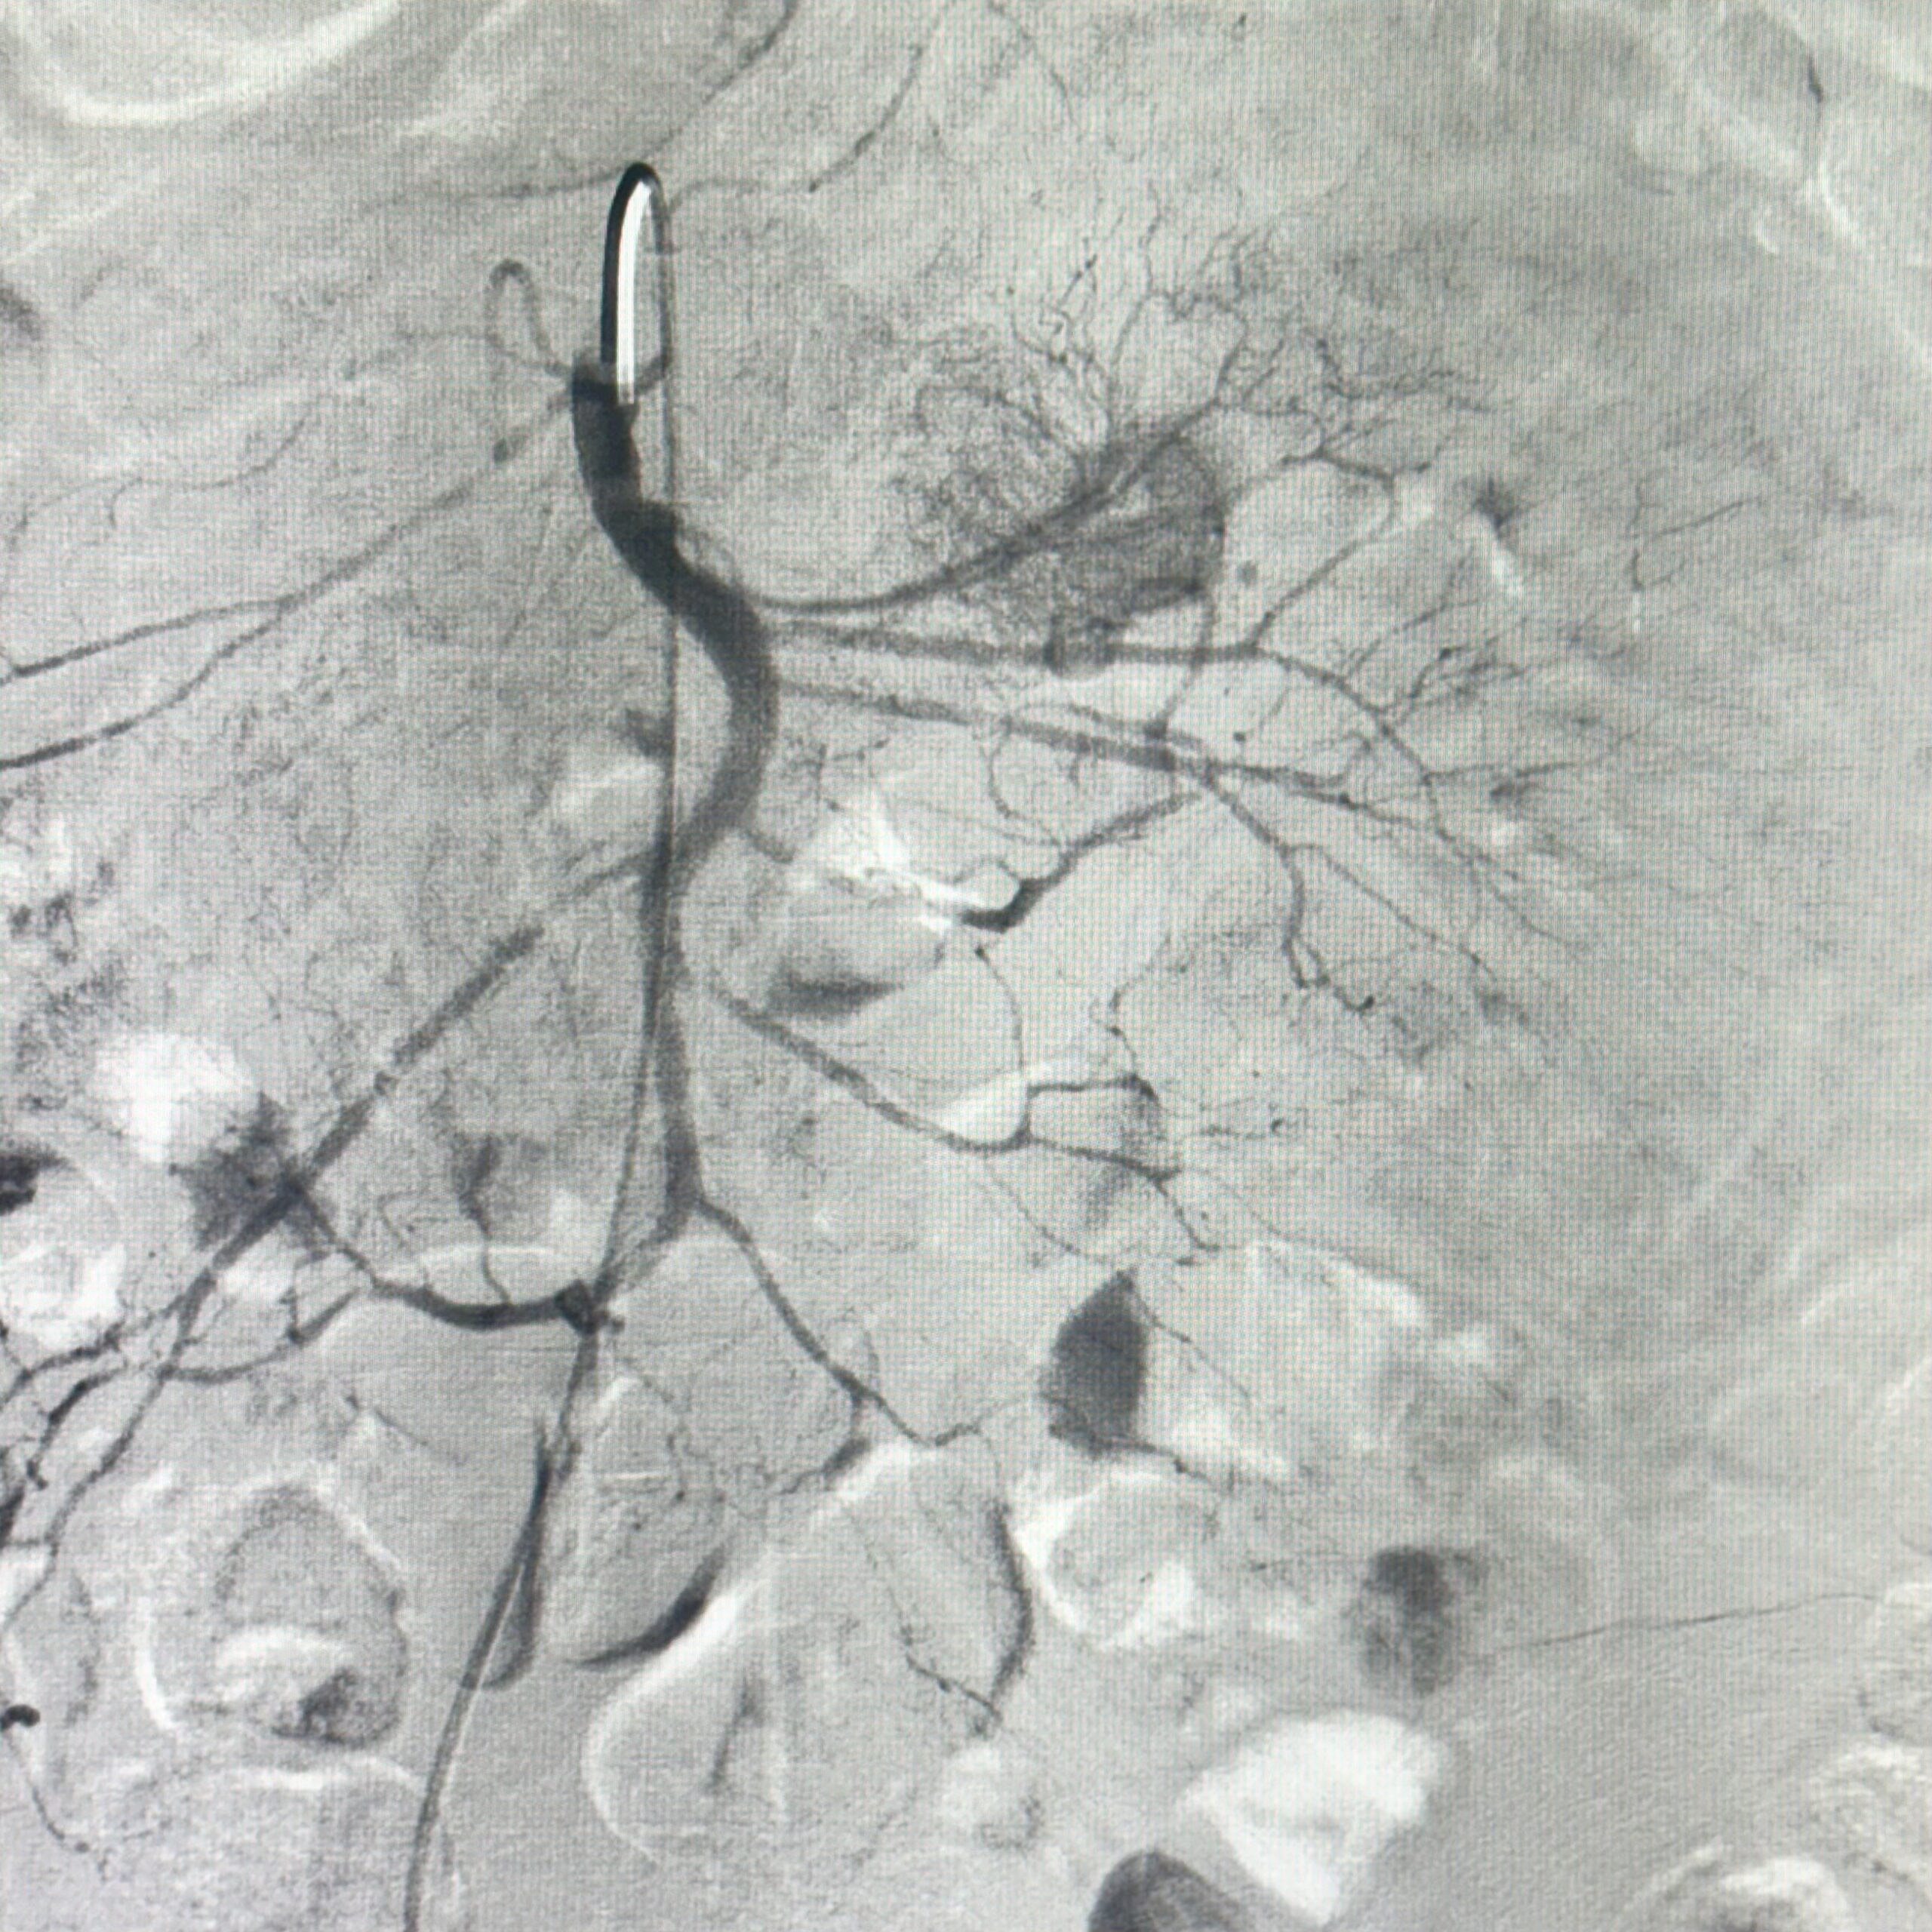

Figura 1: injectare în arteră mezenterică superioară cu evidențierea extravazării substanței de contrast

Video 1: injectare în arteră mezenterică superioară cu evidențierea angiodisplaziei jejunale

Discuţie caz nr 82: Pacient de 68 de ani internat cu 7 zile în urmă pentru hemoragie digestivă inferioară (hematochezie) și anemie secundară (Hb 7.1 mg/dL), care se accentuează progresiv în pofida transfuziilor repetate (Hb 4.9 mg/dL în ziua a cincea de internare).

În ziua a opta de la internare se practică angiografie diagnostică de Arteră Mezenterică Superioară (aspect sugestiv de angiodisplazie jejunală), urmată de embolizare cu particule resorbabile (Gelaspon) a primului ram jejunal. Rezultat optim postprocedural: încetarea HDI, urmată de corectarea progresivă a sindromului anemic (Hb 9,0 mg/dL în ziua a patra postprocedural).